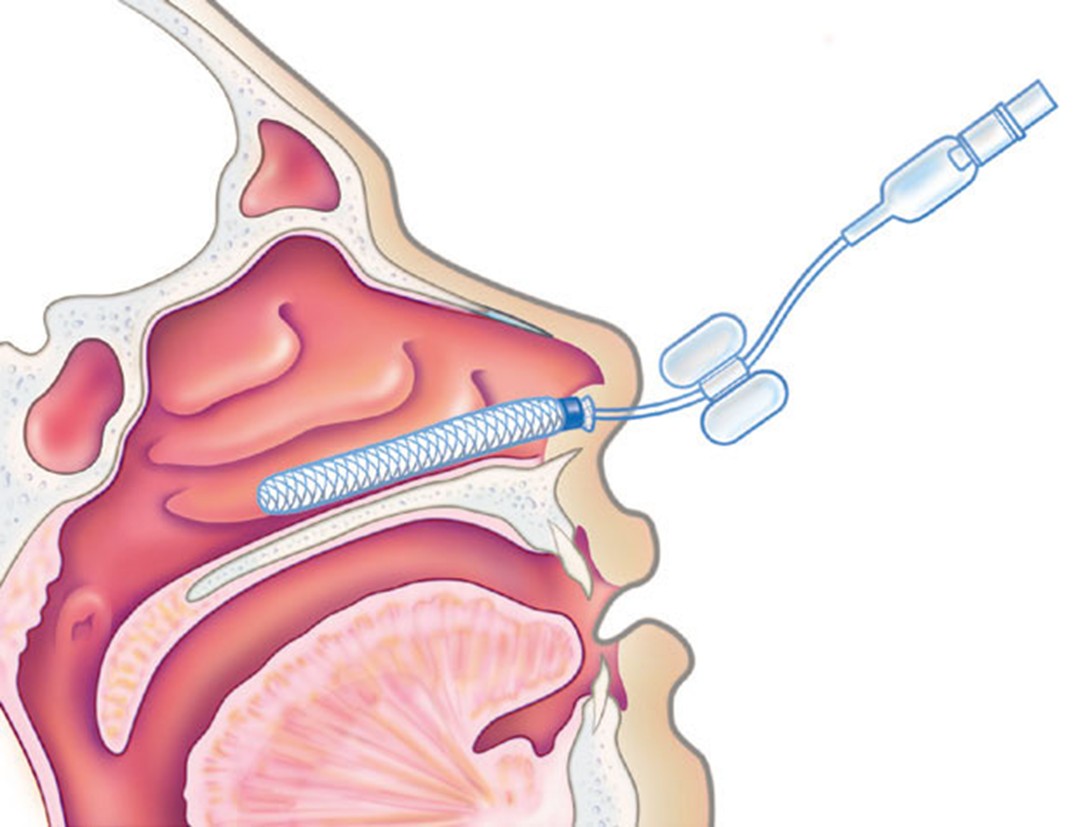

Tamponamento Nasal

Sangramentos mais abundantes que não são controlados com cauterização ou que ocorrem em regiões mais posteriores da cavidade nasal, podem necessitar de tamponamento nasal.

A função do tampão nasal é fazer uma compressão do vaso sanguíneo no local do sangramento para contê-lo havendo uma posterior cicatrização da lesão. Normalmente deixa-se na cavidade nasal pelo período de 48 a 72 horas sendo removido após.